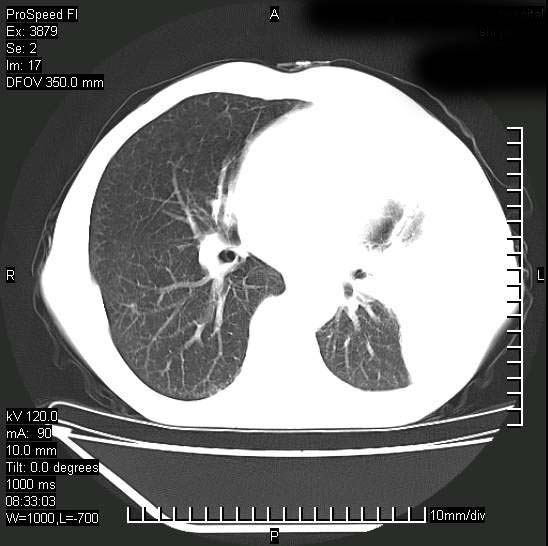

以下是引用37度在2008-6-6 11:20:00的发言:[br]1.包裹性积液,多考虑结核性;[br]2.穿刺术后改变。

以下是引用312nanyang在2008-6-6 15:12:00的发言:[br]基本支持楼主意见[br]疑问?左下肺支气管旁的软组织(16层)密度怎么解释?淋巴结还是斜裂胸膜增厚所致?能否增强进一步检查